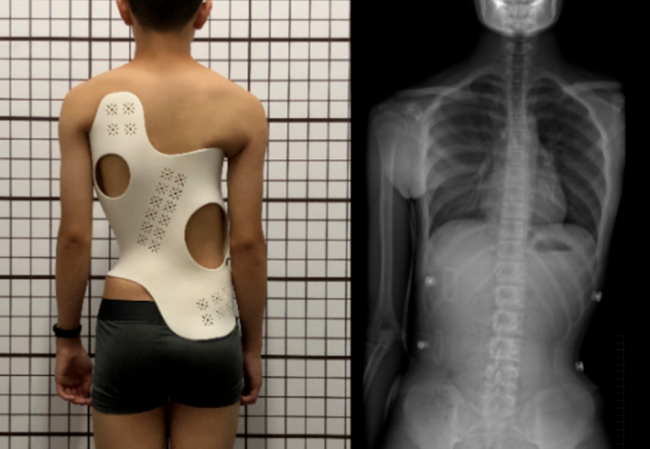

¼¹Öù²àÍäÊÇÒ»ÖÖ³£¼ûµÄ¼¹Öù»ûÐμ²²¡£¬ÁÙ´²Éϳ£ÓÃÁ¢Î»X¹âƬÀ´ÆÀ¼Û¼¹Öù²àÍäµÄÑÏÖØË®Æ½£¬È»¶øÕâÖֹŰåµÄÆÀ¹ÀÒªÁì²¢²»¿ÉÈ«…